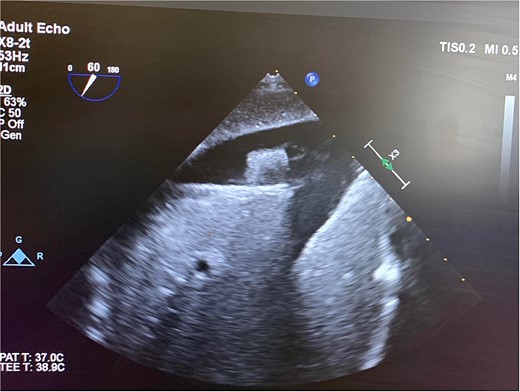

On hospital Day 7, the patient had acute hypoxic respiratory failure. CT chest found a right segmental pulmonary embolism and a retained bullet near the aortic root. A TEE was repeated, this time demonstrating severe aortic insufficiency (Fig. 4), and a bullet in the left coronary cusp. Cardiothoracic surgery was consulted for evaluation and management. The next day, the patient went to the OR for median sternotomy, cardiopulmonary bypass, aortic root repair with patch, re-attachment of the left coronary cusp, and removal of the bullet from the aortic root.

TEE with intracardiac bullet, severe aortic insufficiency. The bullet is labeled by an asterisk, with shadow artifact posterior to the bullet.